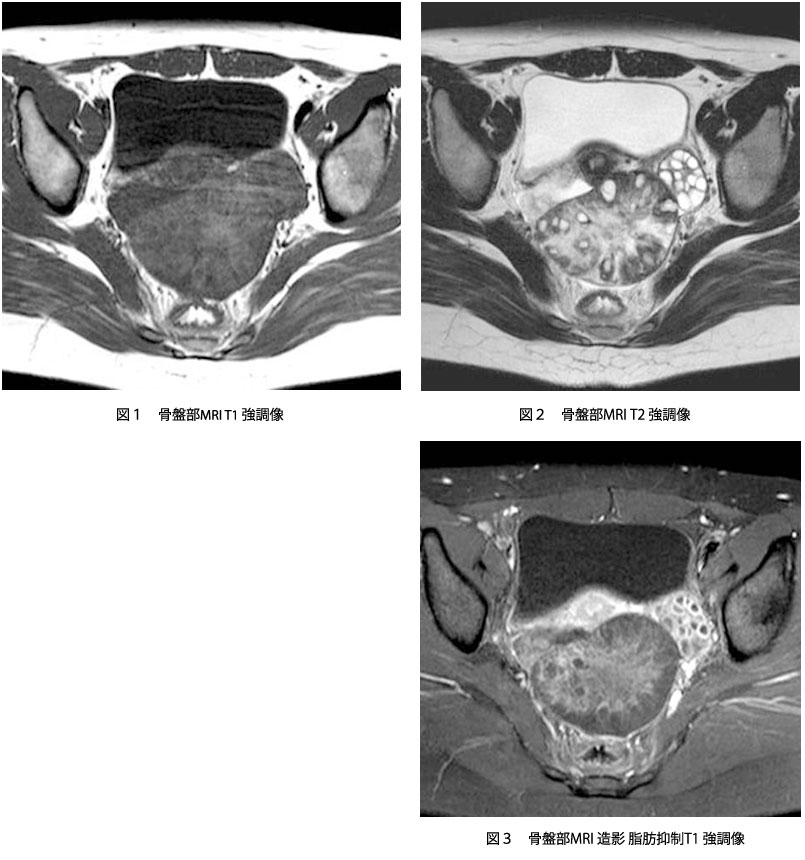

Nuclear Magnetic Resonance (Image). リウマチは関節内に存在する滑膜という組織が異常増殖し、関節内に慢性の炎症を生じる病気で、進行するとさまざまな機能障害を引き起こします 現在、当クリニックでは上腹部MRI検査として、横断像を4シーケンス<T1(in、 out Phase)T2 HeavyT2 DWI>、冠状断. T1強調像(Axial) T2強調像(Axial) 内膜症性嚢胞(チョコレート嚢胞) multiplicity.

MRI ・T2強調像でのjunctional zone. 15分で分かる(?)MRI 古典力学的説明※1 MRI原理へのいざないPart 1 1個のプロトンから15分単位で理解できる(?) 基本的な信号強度 Part 1 プロトン密度、T1、T2と信号強度 ※学部学生は最低でもPart 1を理解すること. 4.mri:撮像法と画像所見 角谷 眞澄 藤永 康成 はじめに 肝疾患の診断にmriが期待されるのは,その優れた 組織コントラスト能によるところが大きい.t1強調像, t2強調像にて肝細胞性結節性病変は様々な信号強度を.